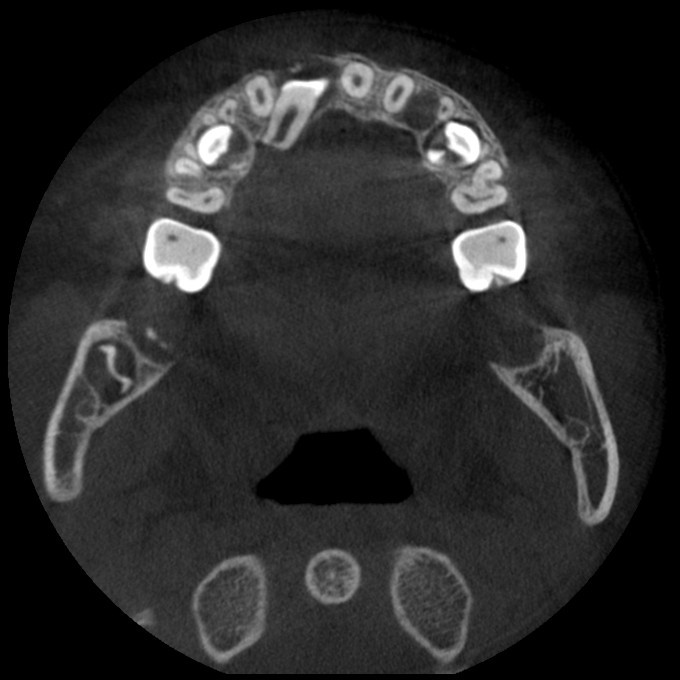

颅颌面CBCT

诊断范围涉及牙体牙髓病、牙周病、阻生牙/多生牙定位、种植牙术前CT评估分析、颞下颌关节CT诊断分析、,颌骨及涎腺疾病、颌面发育畸形、正畸治疗辅助诊断等大部分颌面部疾病,为临床医疗提供强有力的支持。